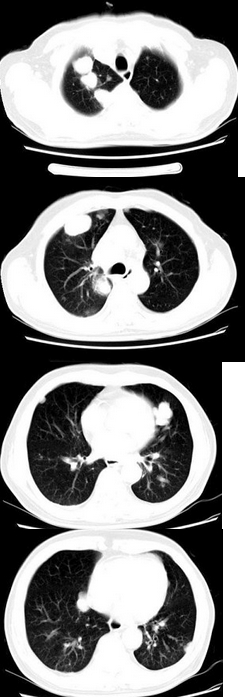

患者31岁,女性,最可能的诊断为( )

A:结节病

B:转移瘤

C:肺泡细胞癌

D:曲霉菌病

E:以上都不是